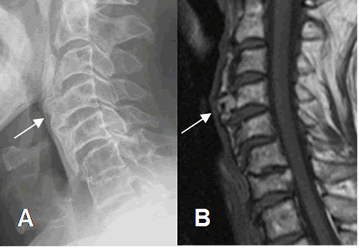

Fig 47. Puentes óseos.

A: Rx lateral y B: RM sagital en T1. Grandes osteofitos cervicales, que forman puentes óseos anteriores.